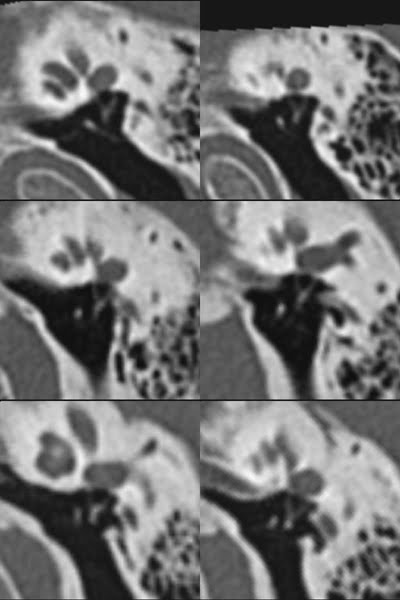

TC de oídos (Temporal bone CT)

Esta es una referencia a un trabajo original sobre postprocesado de TAC de oídos mediante reformateo multiplanar doble oblicuo para estudio de estructuras anatómicas complejas que son difíciles de evaluar en planos coronal y axial. Fue publicado en Surgical and Radiologic Anatomy en el año 2009. Podéis consultar el trabajo original en Oblique multiplanar reformation in multislice temporal bone CT. Blanco M, Vázquez F, Pumar JM, del Río M, Romero G. Surg Radiol Anat.2009 Jul;31(6):475-9.

En estas imágenes no publicadas se representan los dos oídos, mofológicamente normales, de tres pacientes en cada imagen para constatar la reproductibilidad de la técnica. Hemos elegido planos para el estudio de la cóclea, el complejo incudomaleolar, el estribo y el canal facial.

All patients underwent a multislice temporal bone CT and oblique single slice reformation postprocessing in six proposed different planes corresponding to cochlear basal turn, apical basal turn, malleoincudal complex, stapes, and facial channel. Anatomic and pathologic characterization of some middle and inner ear structures, difficult to evaluate in standard axial and coronal planes, can be improved using this technique.